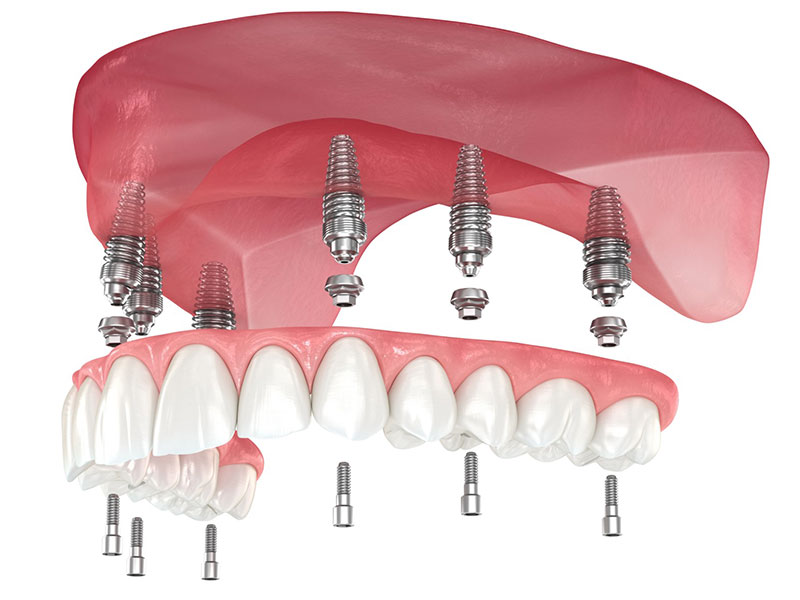

„All-on-4“ concept u oralnoj hirurgiji i implantologiji koristi se za rekonstrukciju i nadoknadu zuba kod pacijenta koji su u potpunosti bezubi odnosno nemaju nijedan zub u vilici.

Kao što mu i sam naziv kaže, omogućava rekonstrukciju i nadokandu zuba ugradnjom četiri implantata. Ovaj koncept je razvijen kako bi pružio kvalitetno i dugotrajno rešenje za pacijente koji si izgubili svoje zube.

1. Implantati

Četiri dentalna implantata se postavljaju u specifičnim pozicijama u vilici. Nakon ugradnje implantata, ukoliko uslovi to dozvoljavaju, pacijent sutradan ili nakon par dana dobija privremene zube. Intervencija se izvodi u lokalnoj anesteziji i potpuno je bezbolna.

Nakon postavljanja implantata, sledi proces osteointegracije odnosno srastanje implantata i kosti. To je period 4 do 6 meseci kada govorimo o gornjoj vilici, odnosno 3 do 4 meseca nakon ugradnje implntata u donjoj vilici. Nakon tog perioda, izrađuje se protetski rad koji se trajno fiksira na ugrađene implntate.

„All-on-6“ koncept sličan „All-on-4“ u stomatologiji i oralnoj hirurgiji, ali umesto četiri implantata koristi šest dentalnih implantata kao osnovu za rekonstrukciju potpunog niza zuba u jednom ili oba zubna luka. Ovaj koncept se često primenjuje kada postoji potreba za dodatnom stabilnošću i podrškom.

Protokol rada i procedure su identične kao i kod All on 4 koncepta, jedina razlika je razlika u broju postavljenih implantata.